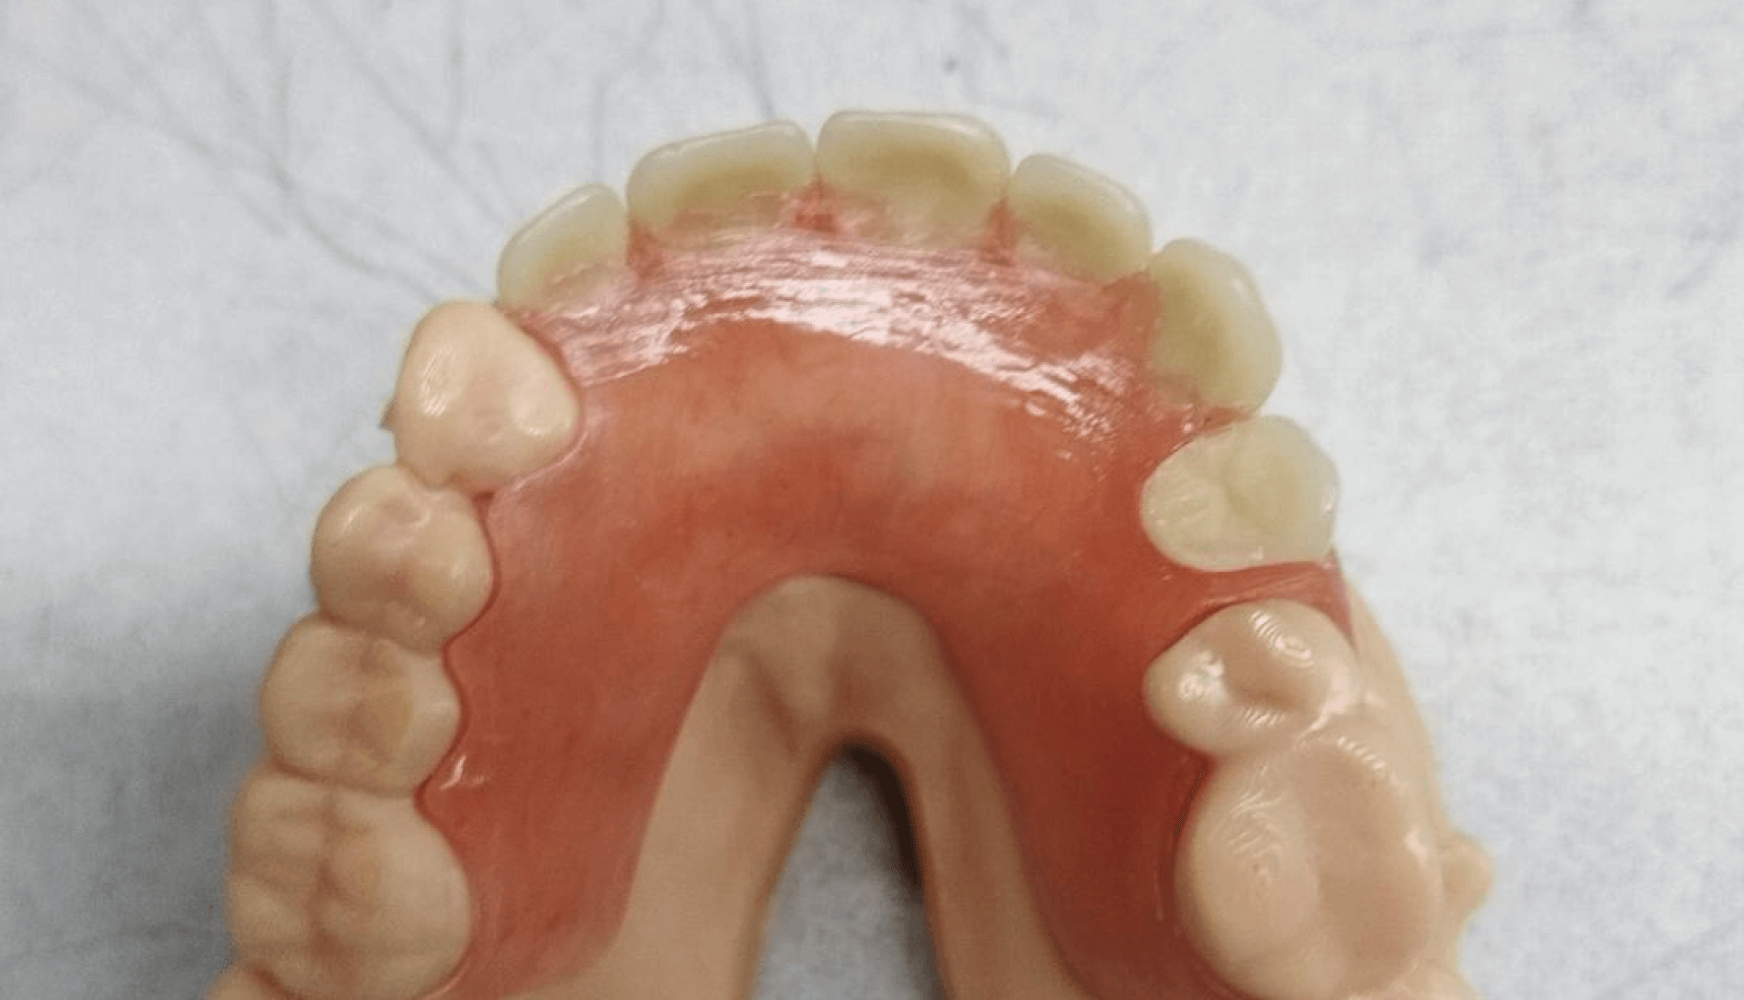

The final partial denture was examined extraorally, and all design specifications were followed (Fig. 4a, 4b, 4c, 4d). The partial was inserted into the patient’s mouth for evaluation, and the patient did not express any pain or general complaints about the feel of the appliance. The patient was instructed to bite, and felt that the bite was slightly incorrect. Minor occlusal adjustment was performed. The partial was reinstated into the patient’s mouth, and the patient expressed that the bite felt correct. The patient was then educated on how to insert and remove the partial. Before dismissal, the patient was reminded that the partial could be adjusted in the future if anything felt uncomfortable or painful in the future.

Figures 4a, 4b, 4c, 4d:

Figure 4a, 4b, 4c, 4d: The fabricated partial denture with its corresponding model. Both tissue shade and tooth shade met the patient’s expectations aesthetically and the overall clasping and fit did so as well.